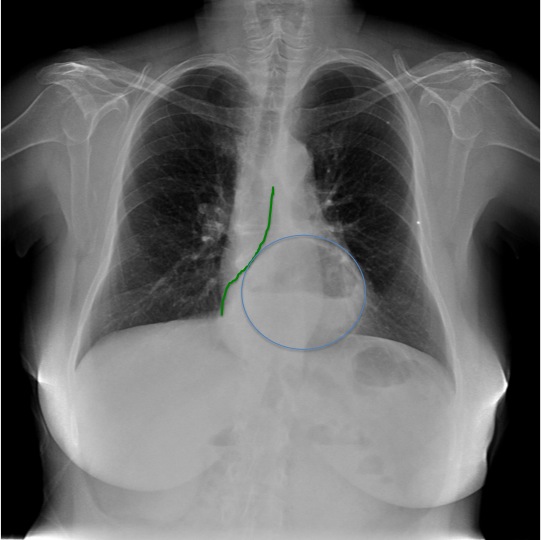

Solución:

1.Imágen retrocardiaca compatible con hernia de hiato.(abajo círculo azul).

2. Desviación de la línea pleuro-acigo-esofágica (abajo en verde).

3. Cifosis dorsal con espondiloartrosis

4. Parénquimas pulmonares sin alteraciones significativas.